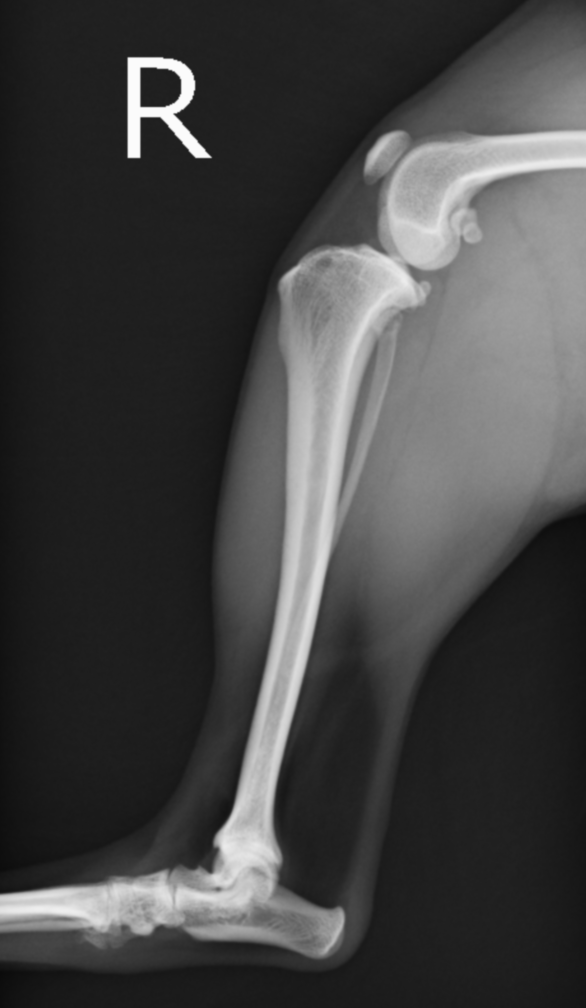

前十字靭帯損傷の膝。大腿骨が尾側に滑り、脛骨の前方変位が認められる

正常肢。大腿骨と脛骨の位置関係が前十字靭帯損傷時と異なり、しっかり連絡性がある